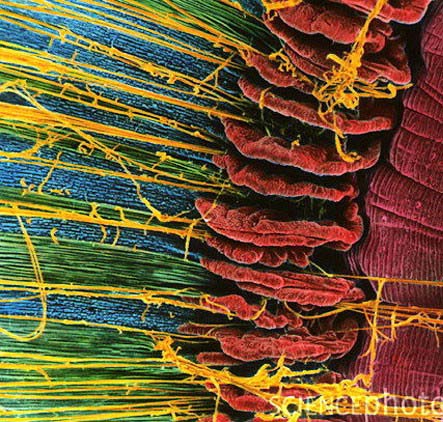

Stereocilia در گوش